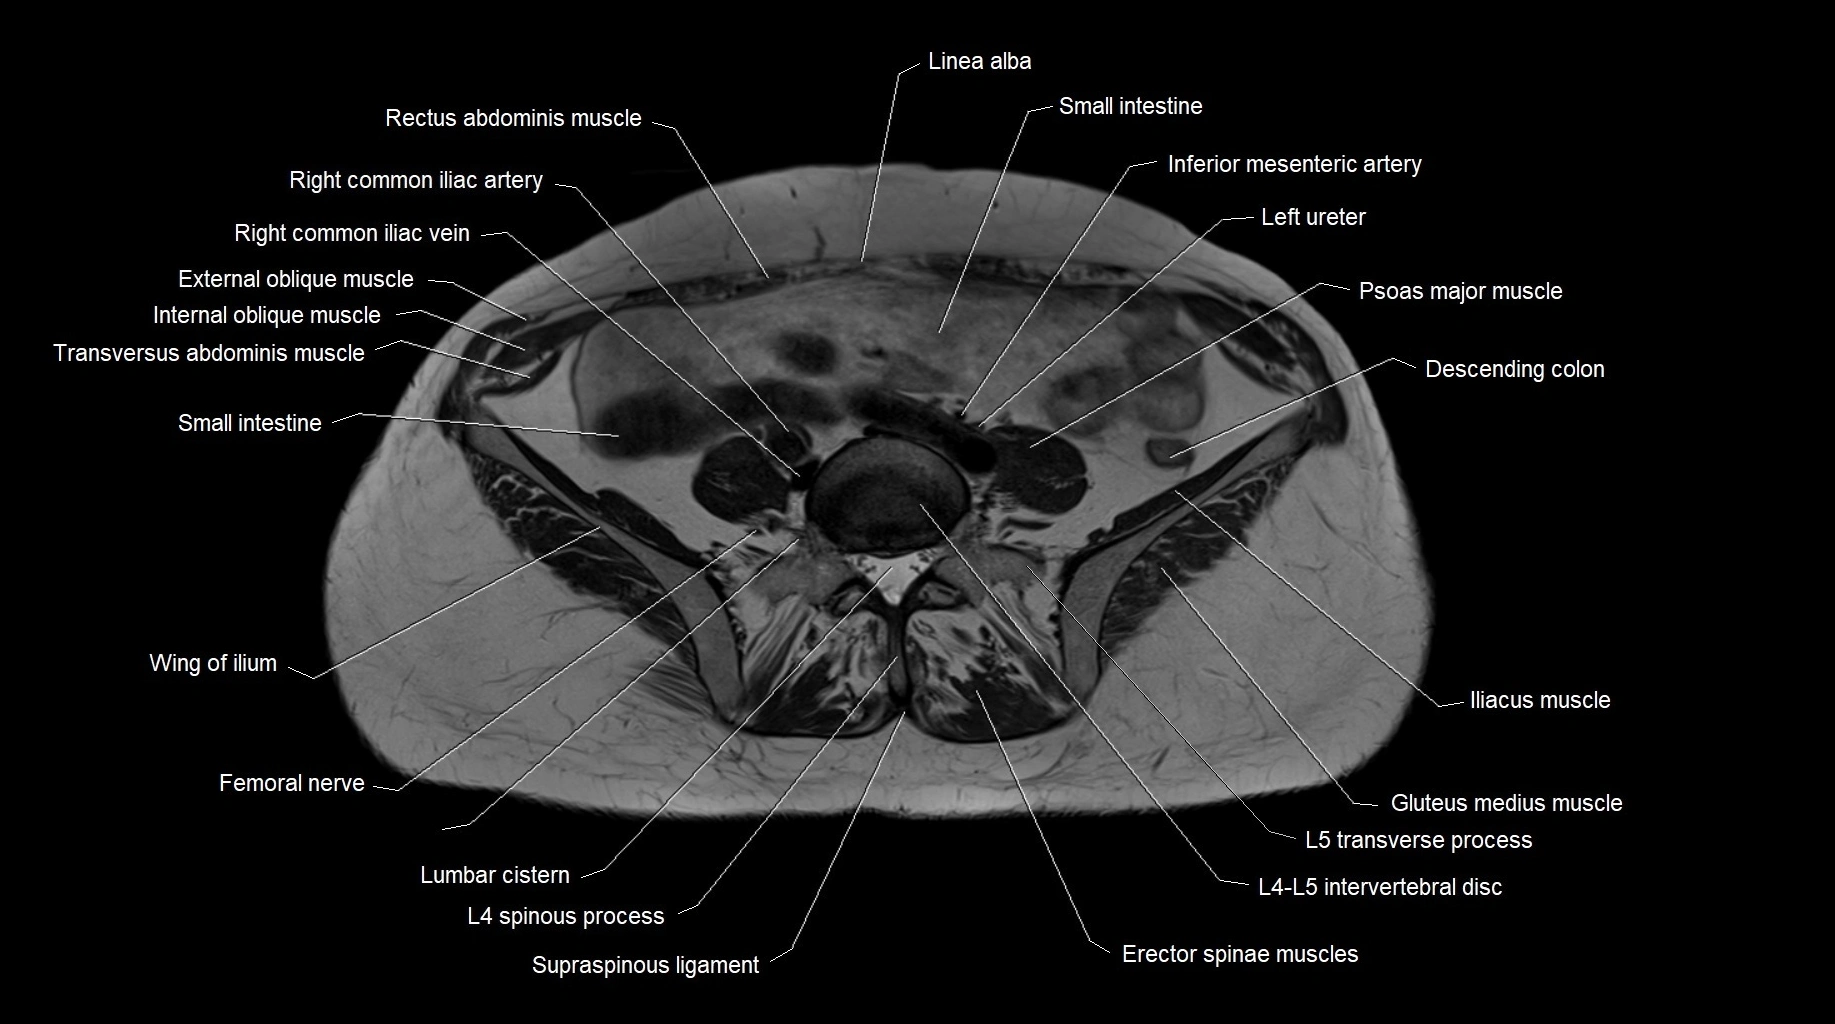

MRI images